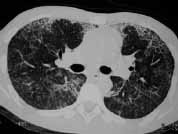

En la radiografía de tórax se evidenciaron infiltrados de ocupación alveolar en parche de distribución periférica. El ecocardiograma mostró miocardiopatía dilatada en fase leve y signos indirectos de hipertensión pulmonar.

Además del antecedente de inyección subcutánea de silicona, y teniendo en cuenta su mayor relación con múltiples inyecciones y mayor cantidad de sustancia, el hallazgo radiológico de infiltrados alveolares periféricos que afectan principalmente la corteza pulmonar es muy sugestivo de embolismo de esta sustancia.

Ante la presencia de edema pulmonar de permeabilidad o hemorragia alveolar estos infiltrados pueden hacerse difusos. La TACAR resalta este hallazgo, y se suma la presencia de engrosamiento de líneas septales probablemente relacionadas con diseminación linfática de silicona.

Figura 5. TACAR: Demuestra la presencia de áreas de vidrio esmerilado difuso e infiltrados alveolares en parches, secundarios a hemorragia alveolar y embolismo por silicona.